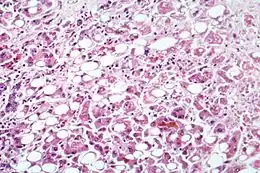

Microscopie

Une hépatite chronique est une pathologie nécrotico-inflammatoire du foie, de sévérité variée, excluant les maladies biliaires (cholangiopathies), la maladie alcoolique (hépatopathie alcoolique) et les stéatohépatites.